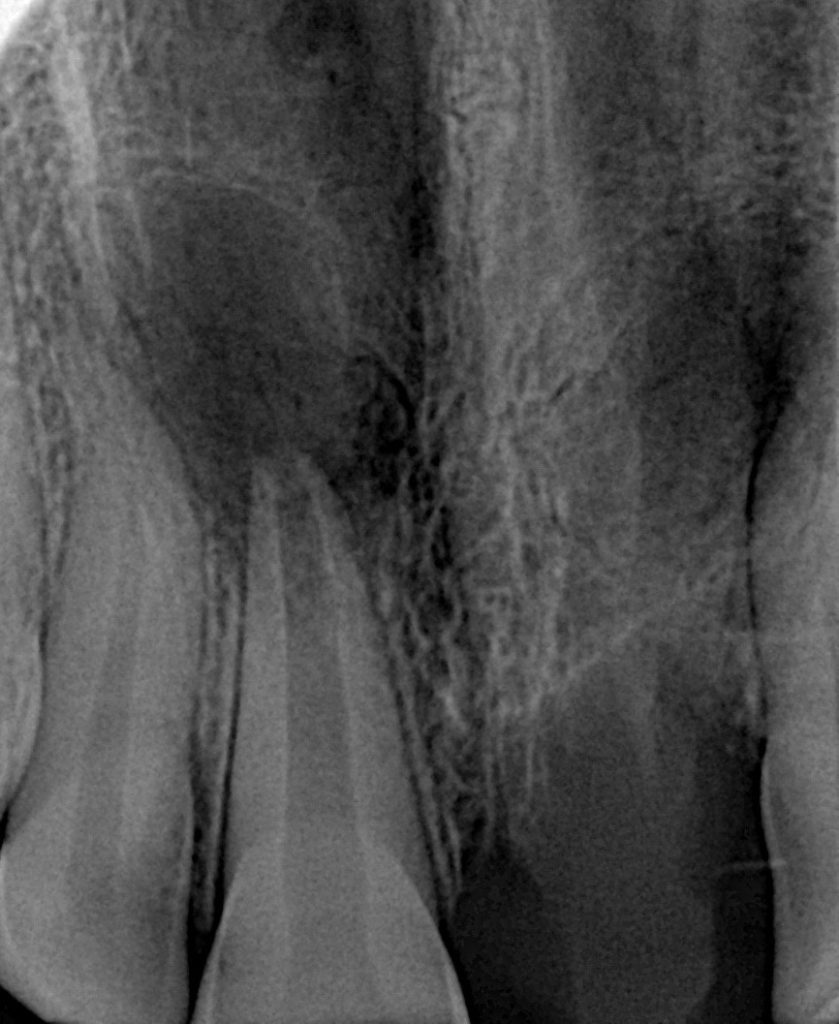

Radiographic Findings:

•Blunderbuss canal

•Thin dentinal walls

•No apical constriction

•Mild periapical changes suggestive of inflammatory root resorption